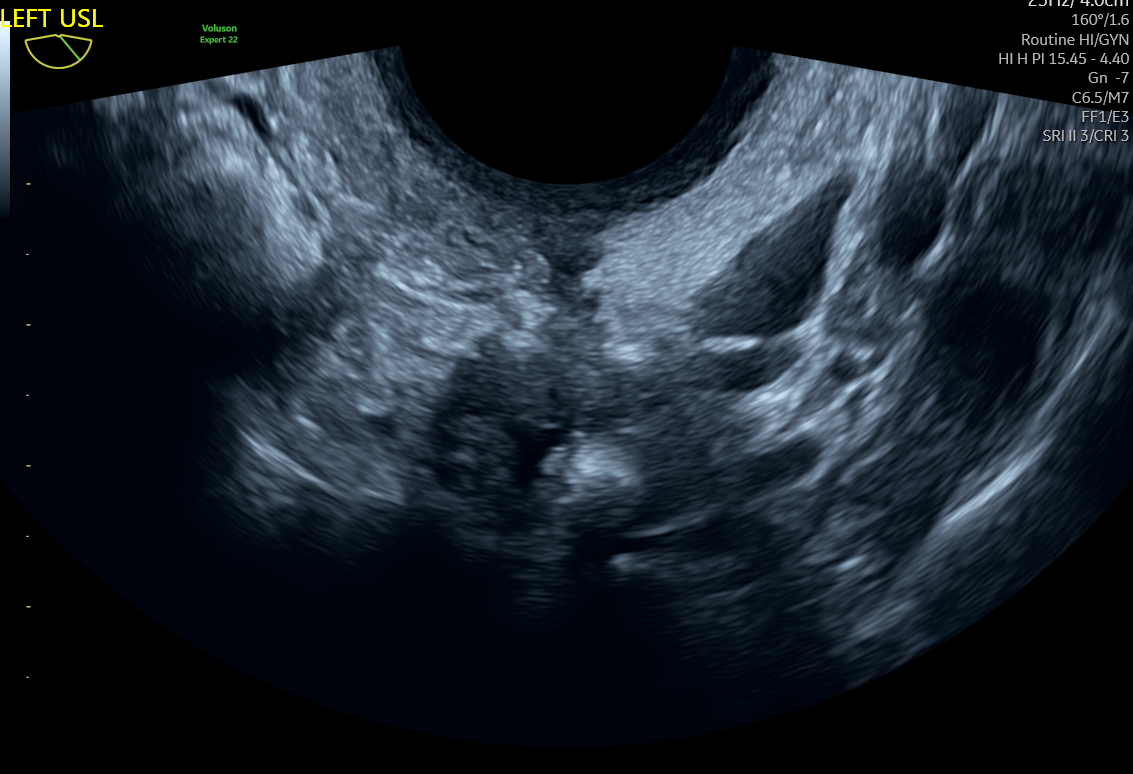

3D Uterus

Endometriosis